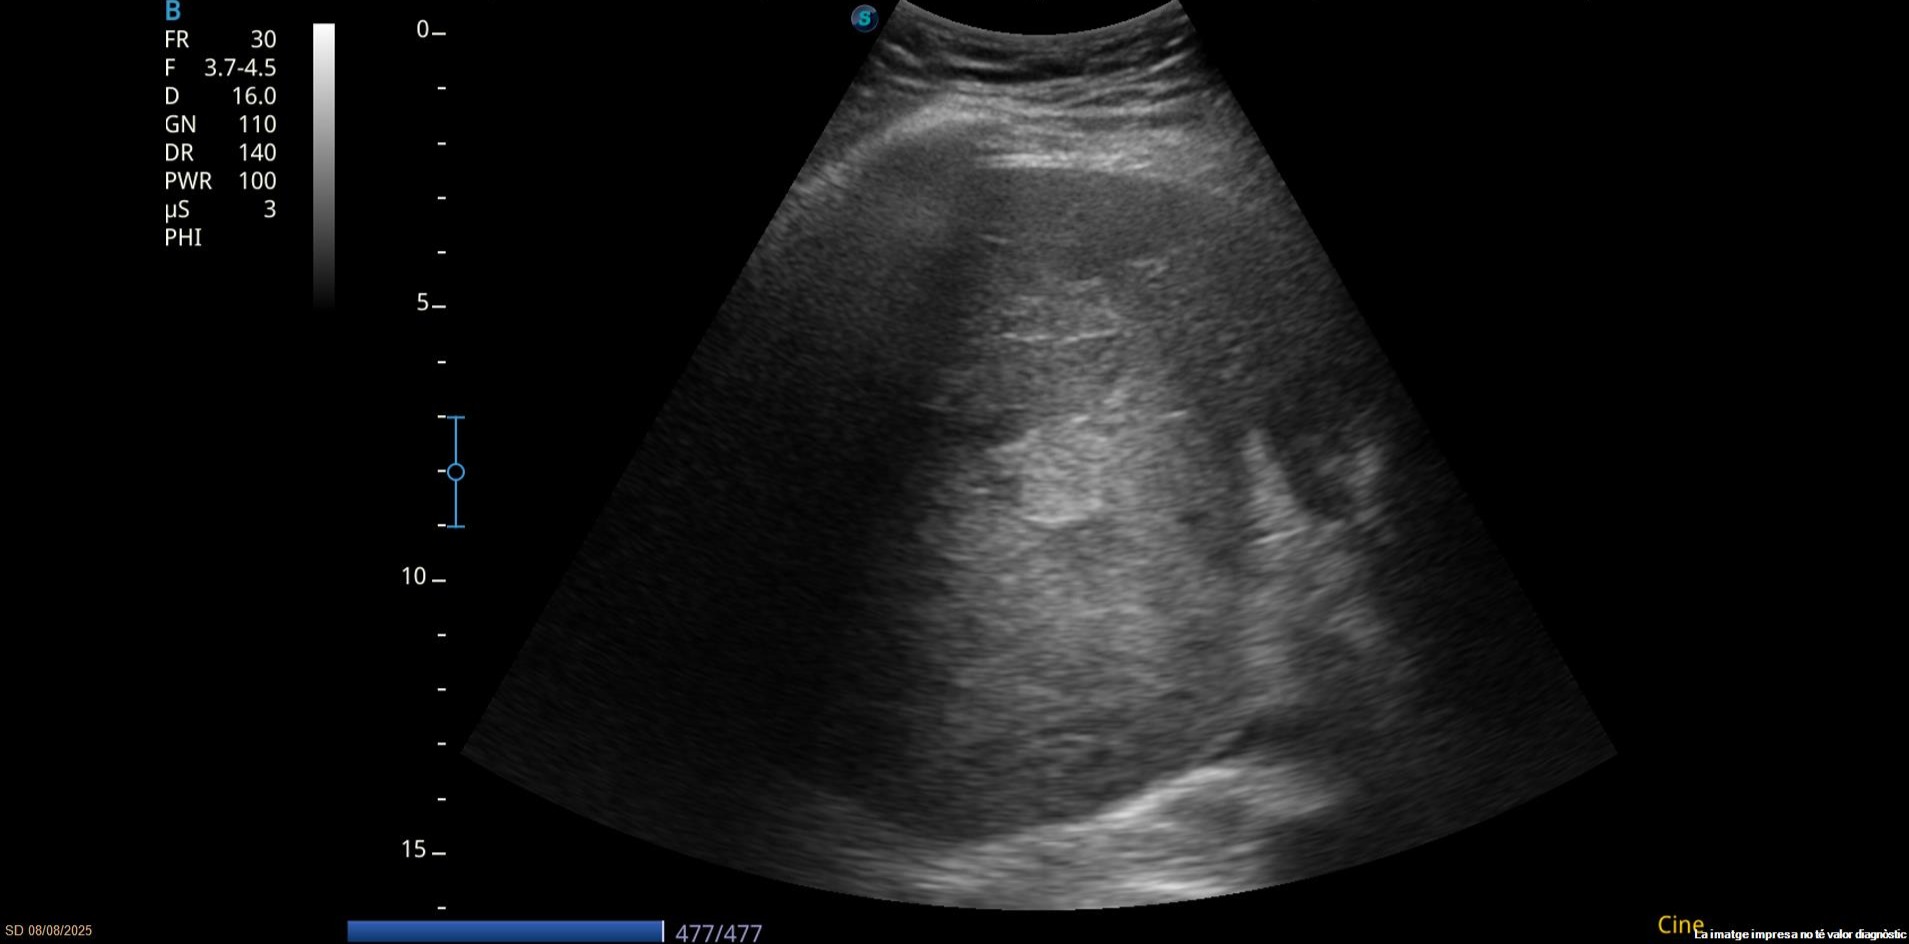

Debido a la alteración analítica se realiza una ecografía abdominal en la consulta.

Hallazgos ecográficos

Eco abdomen: Hígado de tamaño normal, nódulo en LHI de 2 cm y una gran masa heterogénea mal definida de unos 10 cm.

Resto dentro de la normalidad.